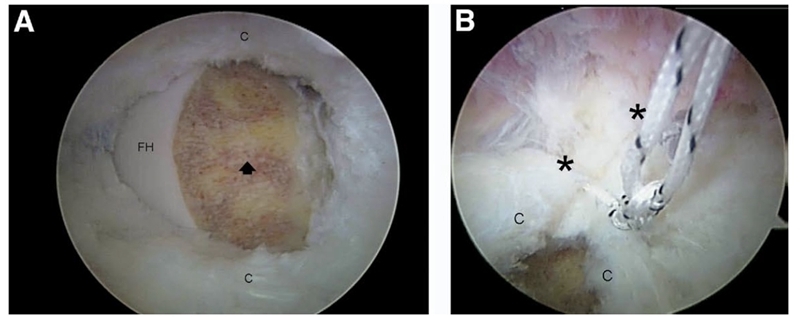

图7.在凸轮型股骨髋臼撞击症中,髋臼软骨分层是由于髋关节屈曲时持续的剪切力造成的。

(A)邻近盂唇撕裂(已经修复,弯曲的开放箭头)的髋臼软骨分层(直箭头)的关节镜图像。(B)病变的基底部可以微骨折并用聚二恶烷酮缝合线(译者注:可吸收缝合线)(星号)缝合修复。(C)已完成的软骨修复(星号)直接覆盖盂唇修复(弯开箭头)。(A 髋臼;FH 股骨头;L 盂唇。)